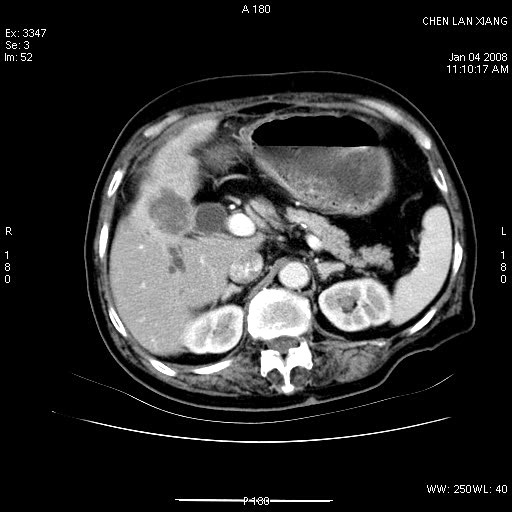

女,76岁,腹痛3-4天,b超示:肝内实性肿物,胆囊强回声,胆总管扩张.

考虑:1、胆总管下端结石伴梗阻性肝内外胆管扩张(肝左叶外侧段肝内胆管多发结石、胆管炎);

2、肿囊癌累及肝,不除外 黄色肉芽肿性胆囊炎。

1 胆总管末端结石伴肝内胆管结石,肝内外胆管扩张。2 胆囊扩大,胆囊壁不规则增厚,内见软组织密度影。考虑:慢性胆囊炎,不除外胆囊癌!

ct所见:1、 肝内胆管结石,肝内外胆管扩张。低位胆道梗阻,胆总管下端结石;2 胆囊扩大,胆囊壁不规则增厚

考虑:胆总管下端结石并肝内外胆管扩张,肝内胆管结石;

标题: 肝右叶病灶

胆囊癌侵犯肝右叶?

1)胆囊癌伴肝脏转移。2)胆总管下端结石、肝内胆管结石伴肝内外胆管扩张。